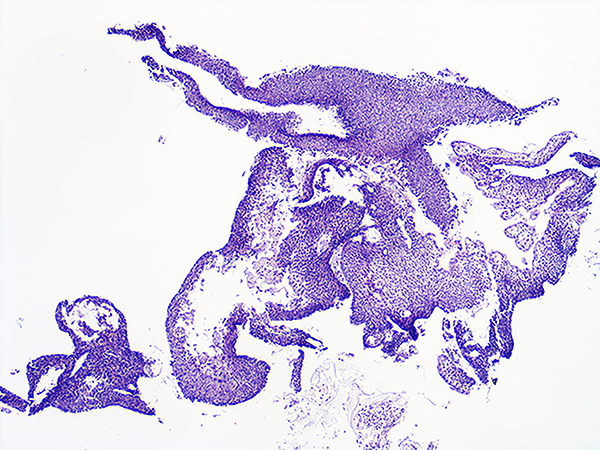

Case 1

Soft Bx CIN 2 10x - Low Power